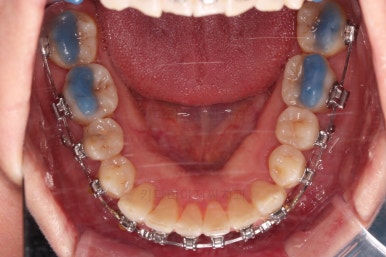

비발치 치료에서 핵심되는 장치가 미니스크류에요.

위 사진에서도 어금니쪽 잇몸 부위를 보시면 아주 작은 금속성 나사머리가 보이실건데요. 나사로 단단히 지탱해주고 치열을 뒤로 당겨주는 원리죠.

치료의 막바지인데도 불구하고 아직 앞니쪽에 틈이 보이죠?

틈새는 가장 마지막에 모이게 될거에요.